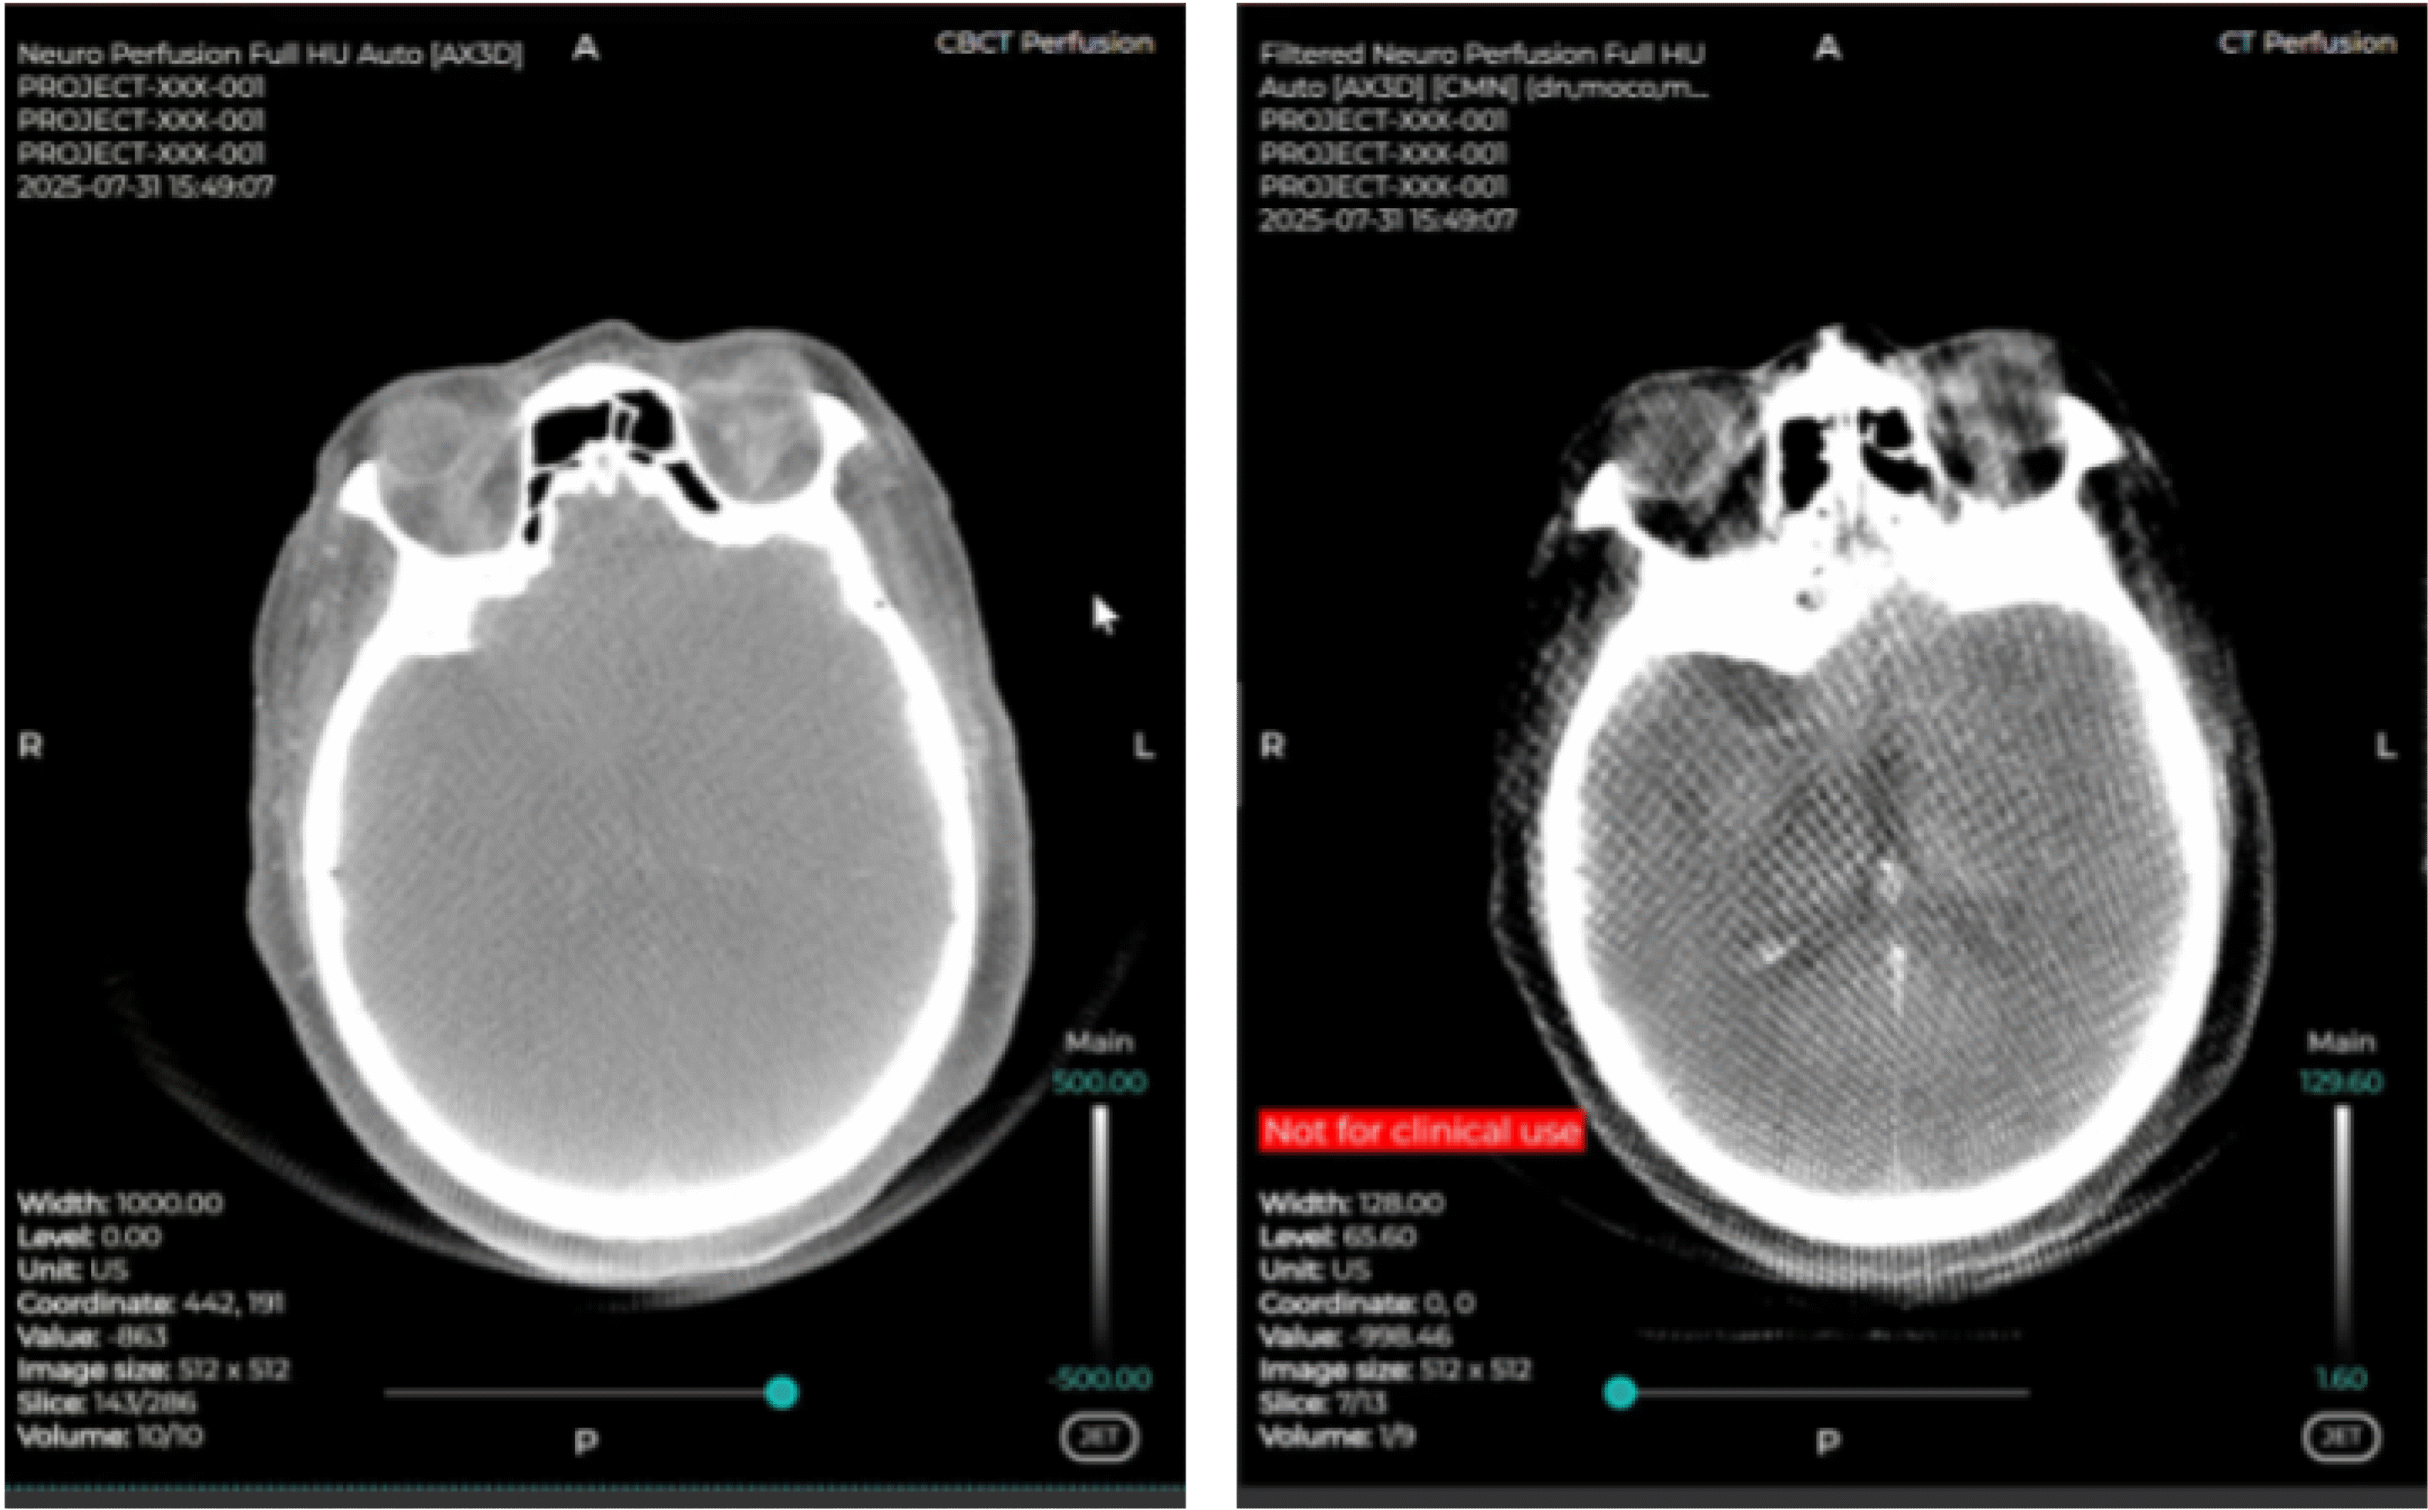

There are approximately 1,500 new cases of a primary brain tumor in Denmark each year, and about 15,000 people live with the diagnosis of primary brain tumor, including both patients in active treatment or follow-up regime or people in full recovery(2). After surgery, management of oncology patients for radiotherapy requires regular imaging follow-up to gauge the success of the treatment as well as the timely discovery of new tumor activity. Department of Radiology (Section of Neuroradiology) at AUH has decided to include perfusion imaging in follow-up which is technically difficult and requires a robust solution to ensure smooth clinical workflow.

CERCARE Perfusion is a fully automated perfusion imaging solution with smart AIF selection powered by artificial intelligence. The technology is grounded in more than 15 years of research in perfusion imaging and is based on the unique approach that accounts for capillary function and integrity allowing to generate both traditional and unique parametric maps that reflect brain tissue oxygenation.